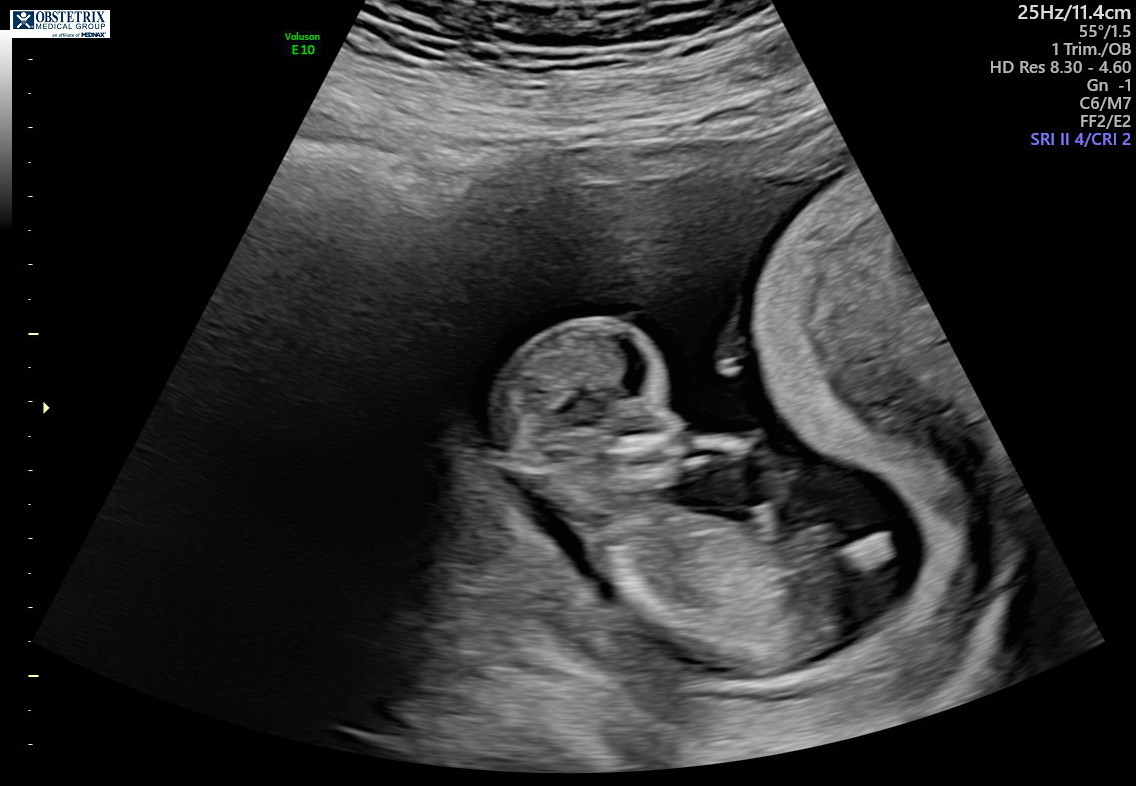

Here is a little boy at 19 weeks! We also got another pic that VERY clearly shows he is a boy which my husband is proudly sending everyone🤣 All measurements were normal but they did bring in doctor who told me it looks like I have a velamentous cord insertion (VCI) for my umbilical cord. She told me it wasn’t a big deal but my OB will tell me more. A quick Google search says it may just be something to monitor more closer to delivery. I’m not too worried- just glad babes is in there and doing well!

All measurements were normal but they did bring in doctor who told me it looks like I have a velamentous cord insertion (VCI) for my umbilical cord. She told me it wasn’t a big deal but my OB will tell me more. A quick Google search says it may just be something to monitor more closer to delivery. I’m not too worried- just glad babes is in there and doing well!